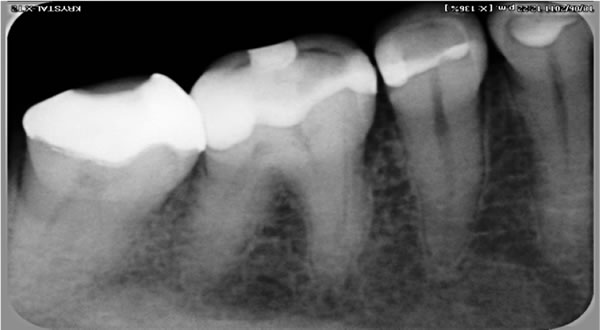

Having the best equipment is very important for successful dental work. Dental Spa Dental Specialists uses state-of-the-art digital imaging equipment for main intra and extra oral images during diagnosis and dental treatment. If you or a loved one need dental surgery, digital imaging helps to target specific conditions.